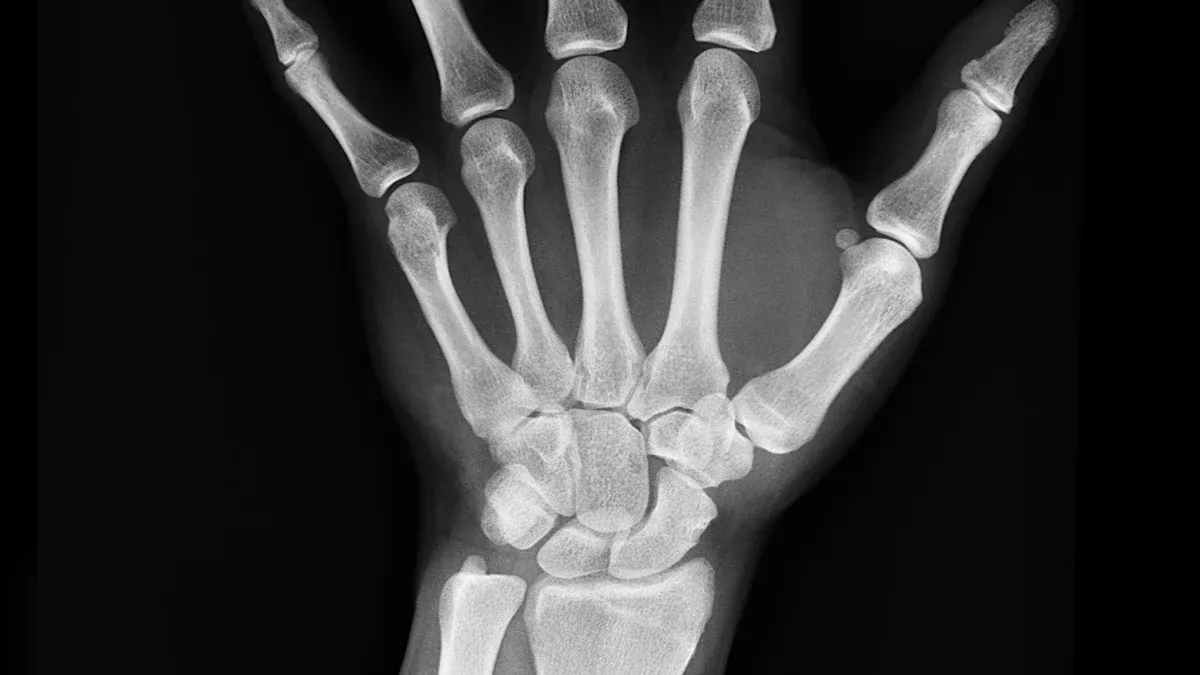

You want strong bones that last a lifetime. Vitamin D3 and K2 work together to help you build healthy bones and keep them strong. When you take vitamin D3, your body absorbs more calcium from food. K2 makes sure that calcium goes into your bones, not your arteries. This teamwork helps you promote bone health and avoid problems later in life.

You want to avoid broken bones as you get older. Vitamin D3 and K2 help lower your risk of fractures by making your bones tougher. D3 helps your body absorb calcium, while K2 activates proteins that move calcium into your bones.

You can see how these vitamins help your bones use calcium the right way. Studies show that people who take vitamin D3 (800-1000 IU/day) have a pooled relative risk of 0.87 for fractures, which means fewer broken bones compared to those who do not supplement.